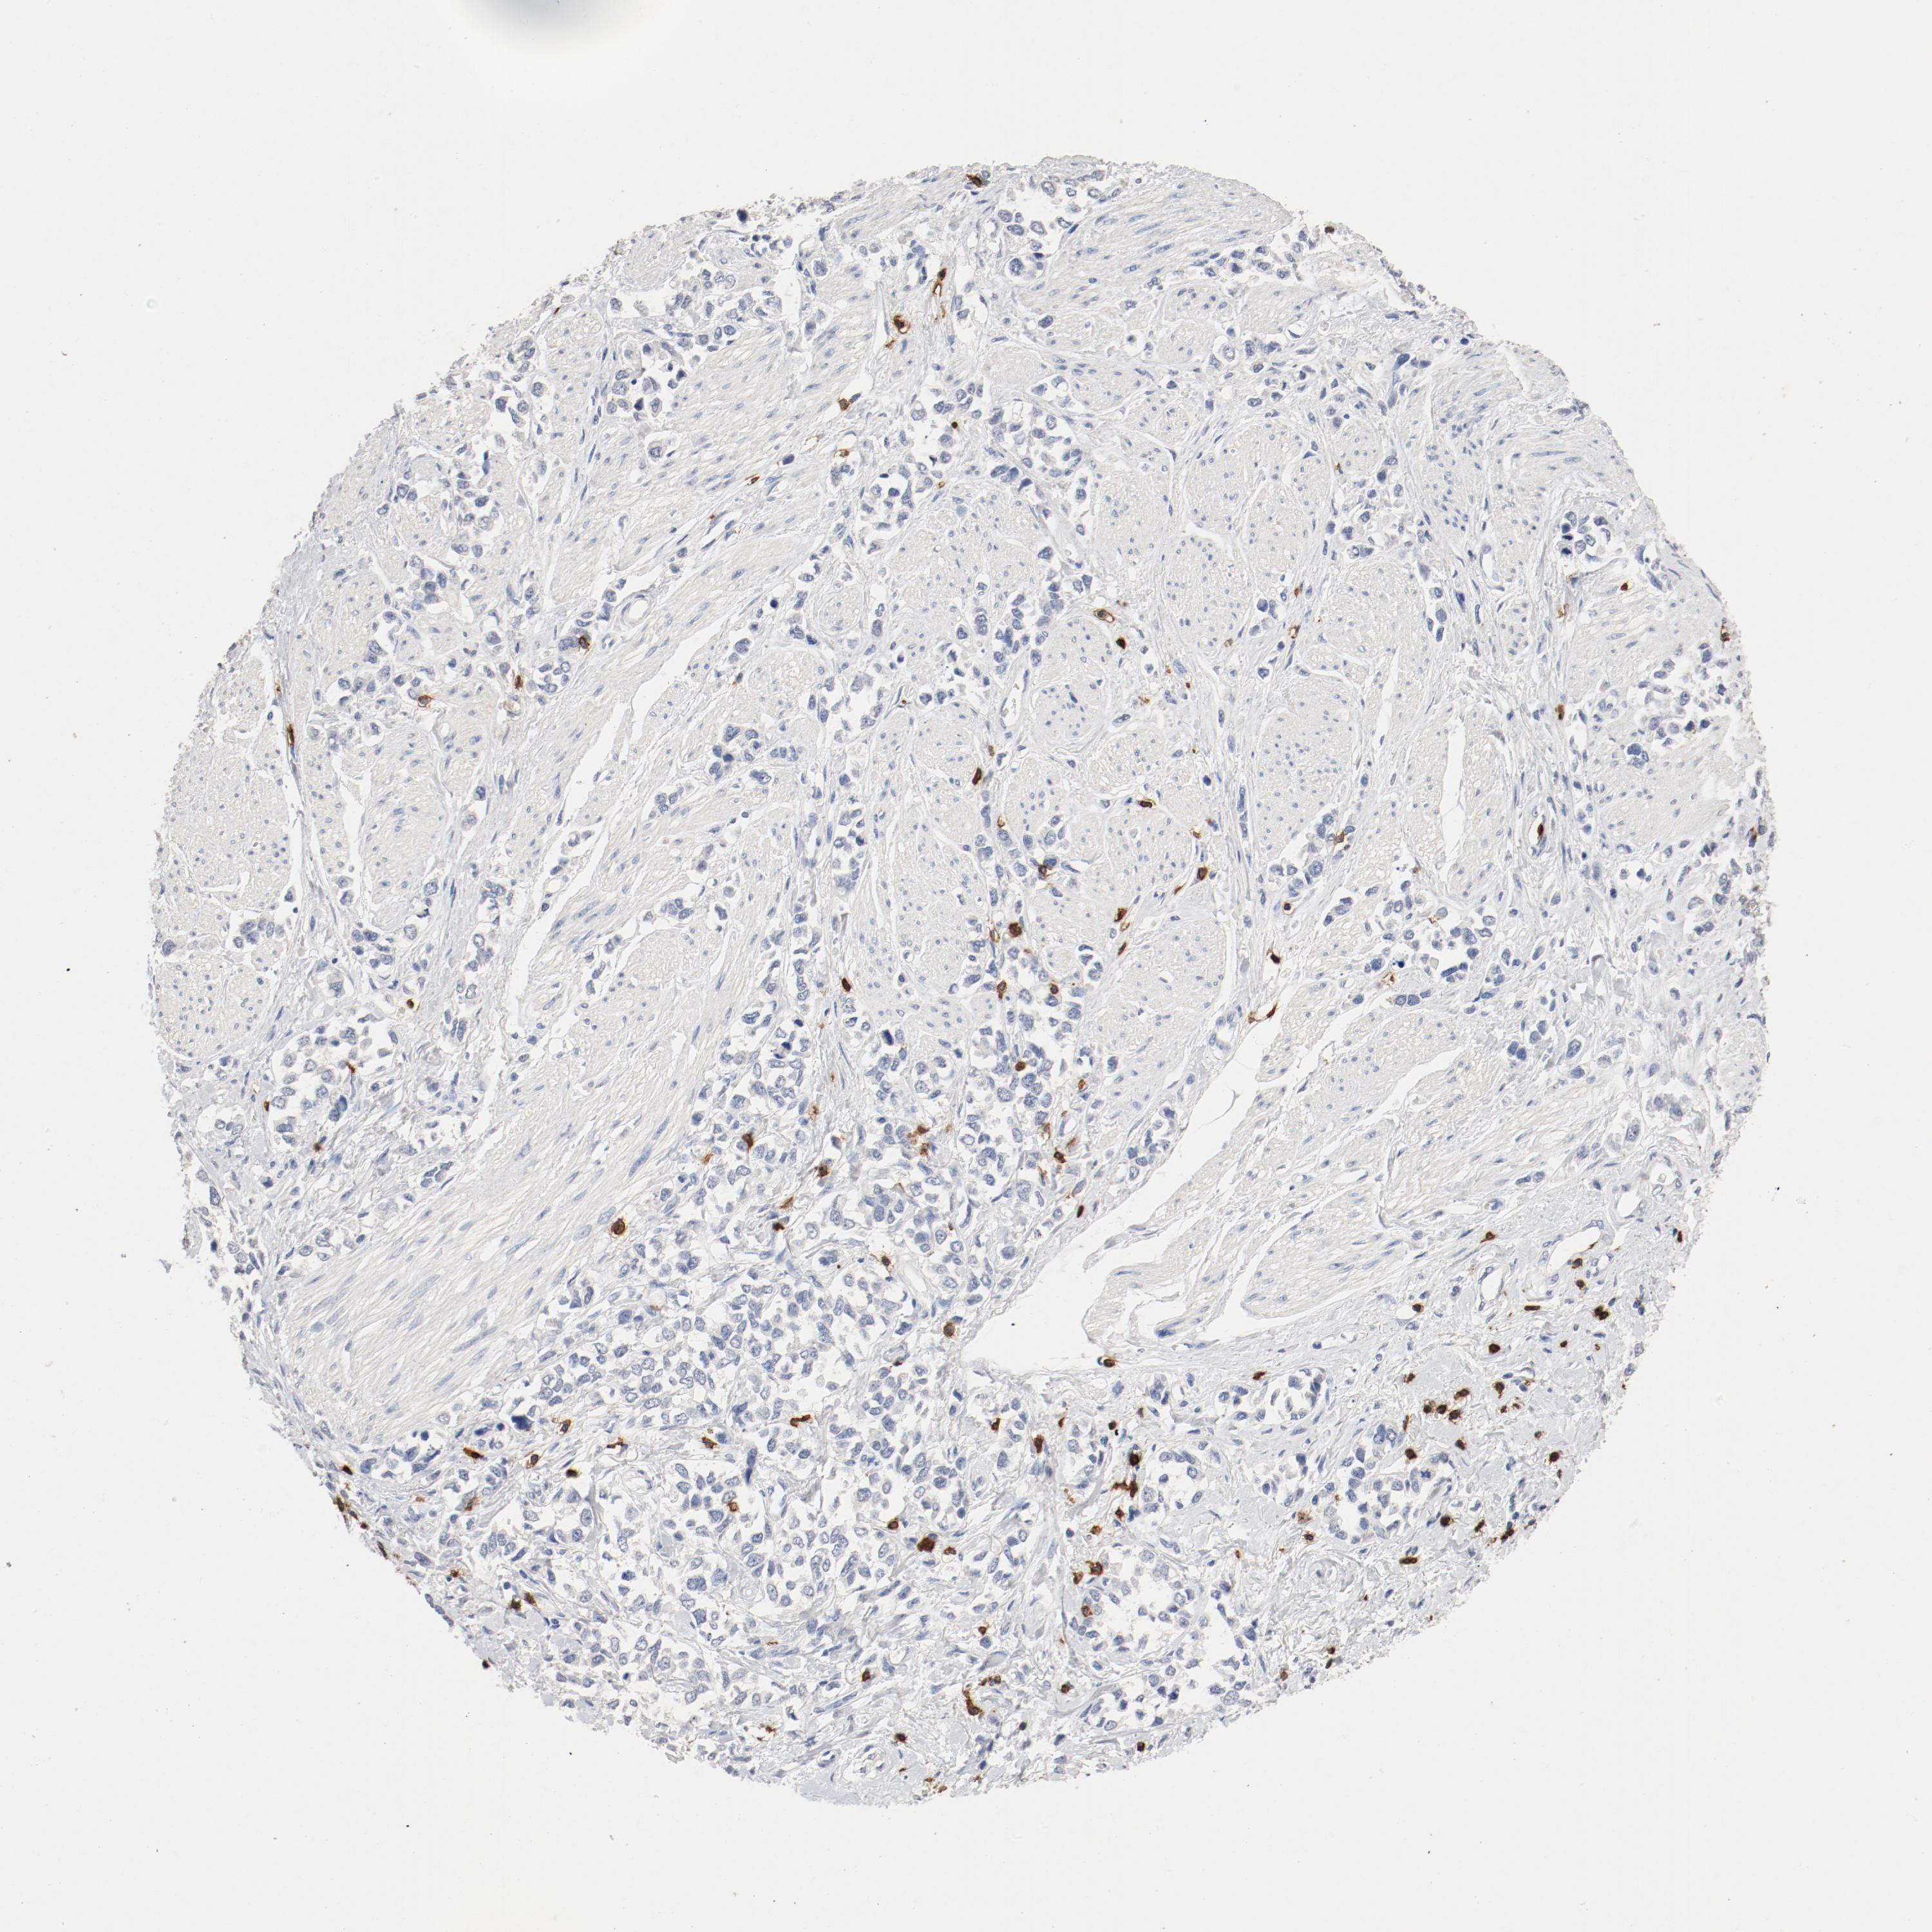

STOMACH CANCER - Protein expressioni

A mouse-over function shows sample information and annotation data. Click on an image to view it in a full screen mode. Samples can be filtered based on level of antibody staining by selecting one or several of the following categories: high, medium, low and not detected. The assay and annotation is described here.

Note that samples used for immunohistochemistry by the Human Protein Atlas do not correspond to samples in the TCGA dataset.

Antibody stainingi

Antibody staining in the annotated cell types in the current human tissue is reported as not detected, low, medium, or high, based on conventional immunohistochemistry profiling in selected tissues. This score is based on the combination of the staining intensity and fraction of stained cells.

Each image is clickable and will lead to virtual microscopy that enables deeper exploration of all samples and also displays staining intensity scores, fraction scores and subcellular localization as well as patient and tissue information for each sample.

Antibody HPA008750

Antibody CAB004651

Staining

High

Medium

Low

Not detected

Intensity

Strong

Moderate

Weak

Negative

Quantity

>75%

75%-25%

<25%

None

Location

Nuclear

Cytoplasmic/membranous

Cytoplasmic/membranous,nuclear

Adenocarcinoma, NOS

Adenocarcinoma, High grade